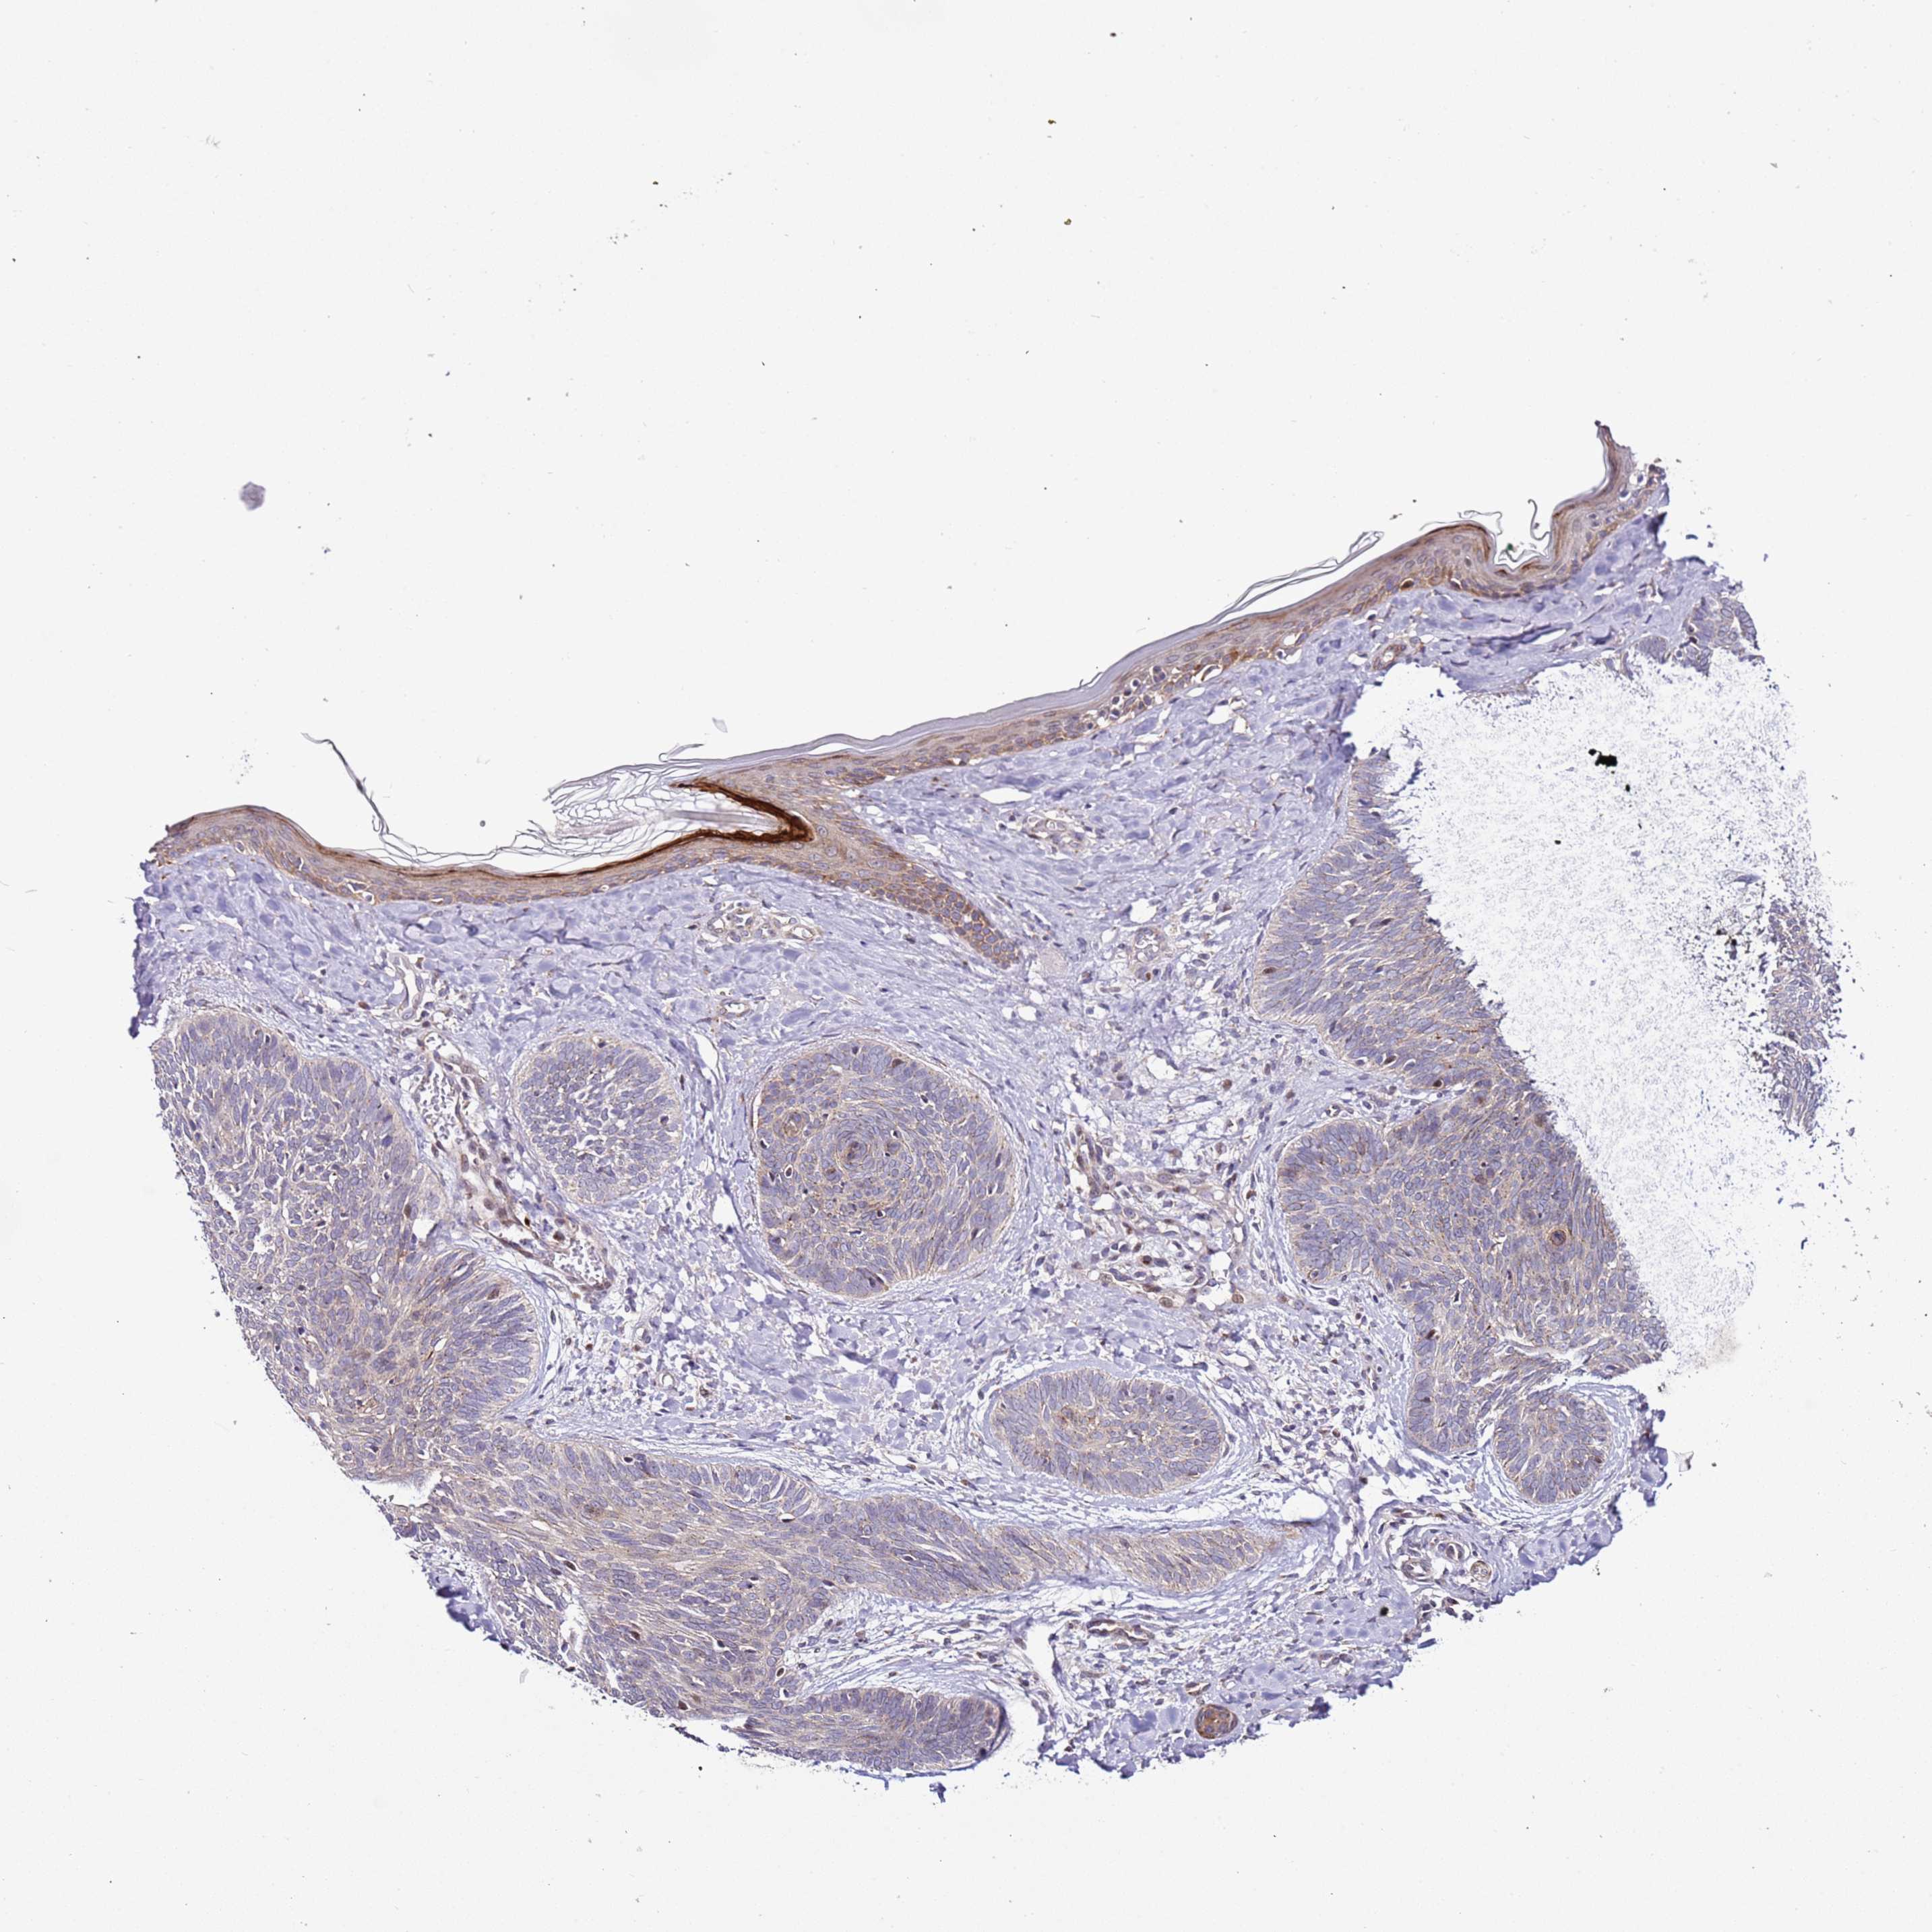

Basal cell and squamous cell cancer

SKIN CANCER - Protein expressioni

A mouse-over function shows sample information and annotation data. Click on an image to view it in a full screen mode. Samples can be filtered based on level of antibody staining by selecting one or several of the following categories: high, medium, low and not detected. The assay and annotation is described here.

Each image is clickable and will lead to virtual microscopy that enables deeper exploration of all samples and also displays staining intensity scores, fraction scores and subcellular localization as well as patient and tissue information for each sample.

Antibody HPA047497

Staining

High

Medium

Low

Not detected

Intensity

Strong

Moderate

Weak

Negative

Quantity

>75%

75%-25%

<25%

None

Location

Nuclear

Cytoplasmic/membranous

Cytoplasmic/membranous,nuclear

Squamous cell carcinoma, metastatic, NOS

Squamous cell carcinoma, NOS